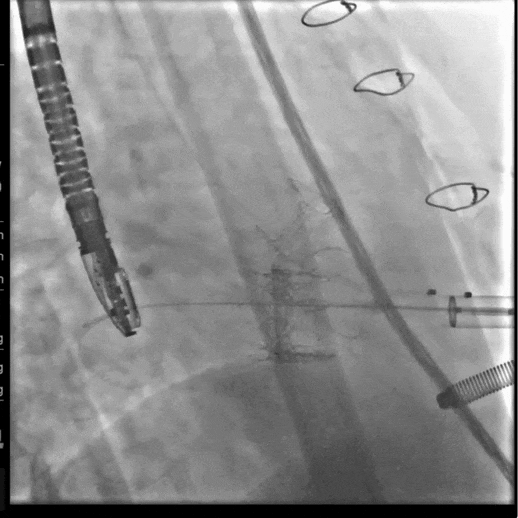

手术采用经心尖入路,术中植入27# RENATUS®球扩式经导管主动脉瓣。瓣膜植入位置理想、功能表现出色,无明显瓣中及瓣周反流,患者症状明显改善。

手术经心尖入路,术中植入25# RENATUS®球扩式经导管主动脉瓣。输送器顺利通过,瓣膜精准释放。瓣膜释放位置理想、形态及功能良好,术后无明显瓣中及瓣周反流等并发症。